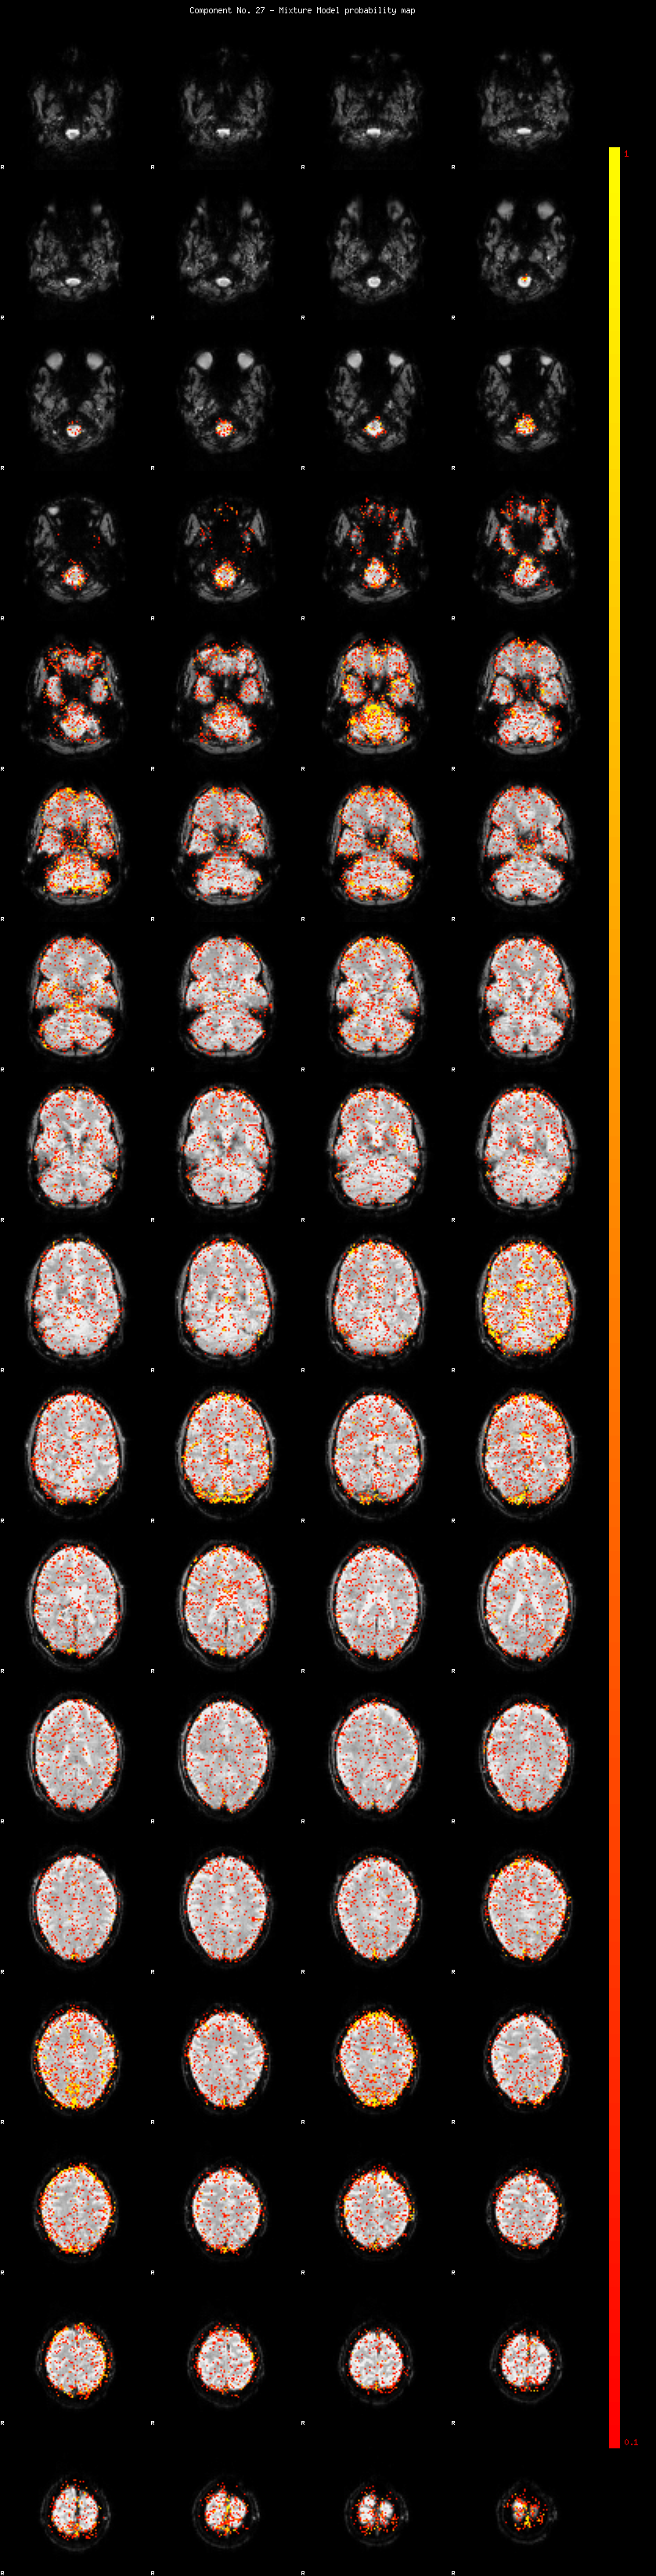

IC_27 Mixture Model fit

Means : 0.000000 2.426278 -2.287118

Vars : 1.000000 1.816460 1.411063

Prop. : 0.926806 0.038188 0.035006